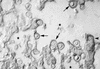

The murine monoclonal antibody (MAb) 18B7 [immunoglobulin G1(kappa)] is in preclinical development for treatment of Cryptococcus neoformans infections. In anticipation of its use in humans, we defined the serological and biological properties of MAb 18B7 in detail. Structural comparison to the related protective MAb 2H1 revealed conservation of the antigen binding site despite several amino acid differences. MAb 18B7 was shown by immunofluorescence and agglutination studies to bind to all four serotypes of C. neoformans, opsonize C. neoformans serotypes A and D, enhance human and mouse effector cell antifungal activity, and activate the complement pathway leading to deposition of complement component 3 (C3) on the cryptococcal capsule. Administration of MAb 18B7 to mice led to rapid clearance of serum cryptococcal antigen and deposition in the liver and spleen. Immunohistochemical studies revealed that MAb 18B7 bound to capsular glucuronoxylomannan in infected mouse tissues. No reactivity of MAb 18B7 with normal human, rat, or mouse tissues was detected. The results show that both the variable and constant regions of MAb 18B7 are biologically functional and support the use of this MAb in human therapeutic trials.